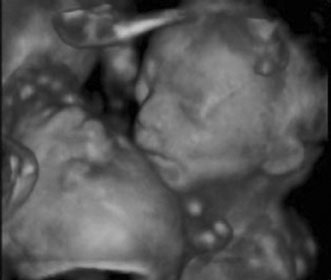

Three-dimensional ultrasound is currently investigational. It is most commonly used at tertiary care centers and is commercially available for patients to obtain a keepsake image of their unborn child. Potential advantages include the ability to visualize fetal anatomy better and possibly change a patient's diagnosis through improved visibility (Figs. 13 and 14). No confirmed adverse biologic effects on patients or instrument operators caused by exposure have been demonstrated.32

Fig. 14. Three-dimensional ultrasound image of twin gestation. Image courtesy of GE Medical Systems.